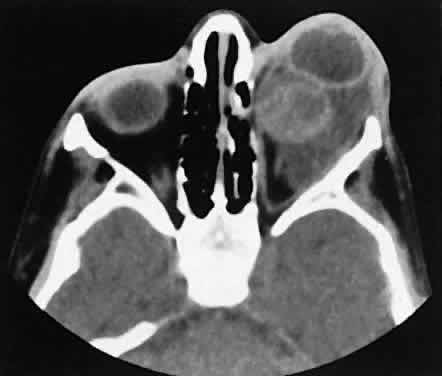

Malignant lesions of the lacrimal gland, conversely, often appear invasive, with bone destruction evident on the CT scan (Fig. 17). Intralesional calcium may be present.63,64 The use of contrast material facilitates detection of lesions that extend beyond the confines of the orbit.

Fig. 17. Adenocarcinoma of the lacrimal gland. A. Unenhanced axial view shows the speckled calcification of a lacrimal gland tumor. B. Contrast-enhanced view at about the same level shows intense enhancement and vascularity. In axial views at a higher level, an unenhanced scan (C) is unremarkable, although a contrast-enhanced view (D) at the same level highlights intracranial extension (arrows). E. Reconstructed coronal view has bone destruction with extension into the intracranial and temporalis fossae.